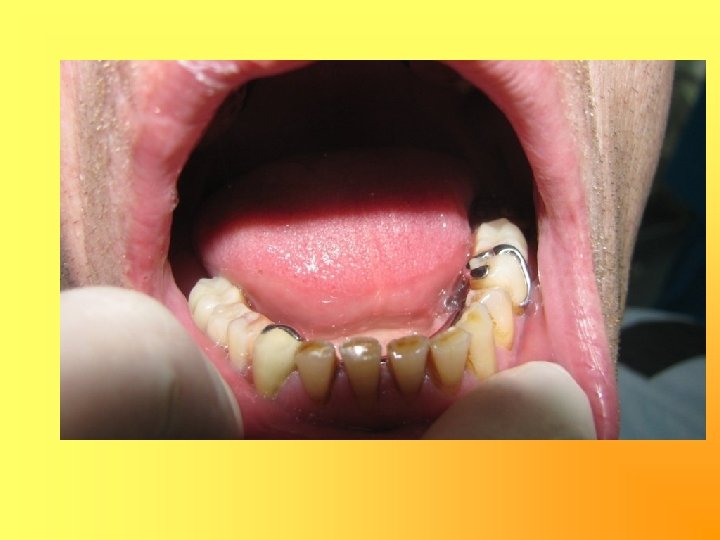

Изготовление культевой штифтовой вкладки: на корни 11, 12 19

20